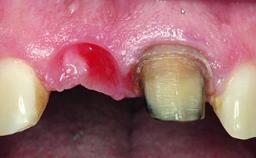

A healthy 37-year-old female patient was referred for a consultation on the replacement of missing tooth 21 with an implant-supported restoration. She stated that several years previously the tooth had been traumatically avulsed following a motor vehicle accident. The tooth was replaced with a three-unit fixed partial denture (FPD) immediately afterwards. Over time, she became disillusioned with the FPD and looked for a different option, including orthodontic therapy. She presented still in her orthodontic appliances, with the pontic sectioned free from the FPD but attached to the archwire. Her orthodontist felt that orthodontic treatment had been successfully completed, but nevertheless referred her before removing the appliances in case adjustments were necessary.

Soft Tissue Anatomy Intact Defective

Bone Volume Horizontally and vertically sufficient Horizontally deficient Deficient vertically or deficient vertically AND horizontally